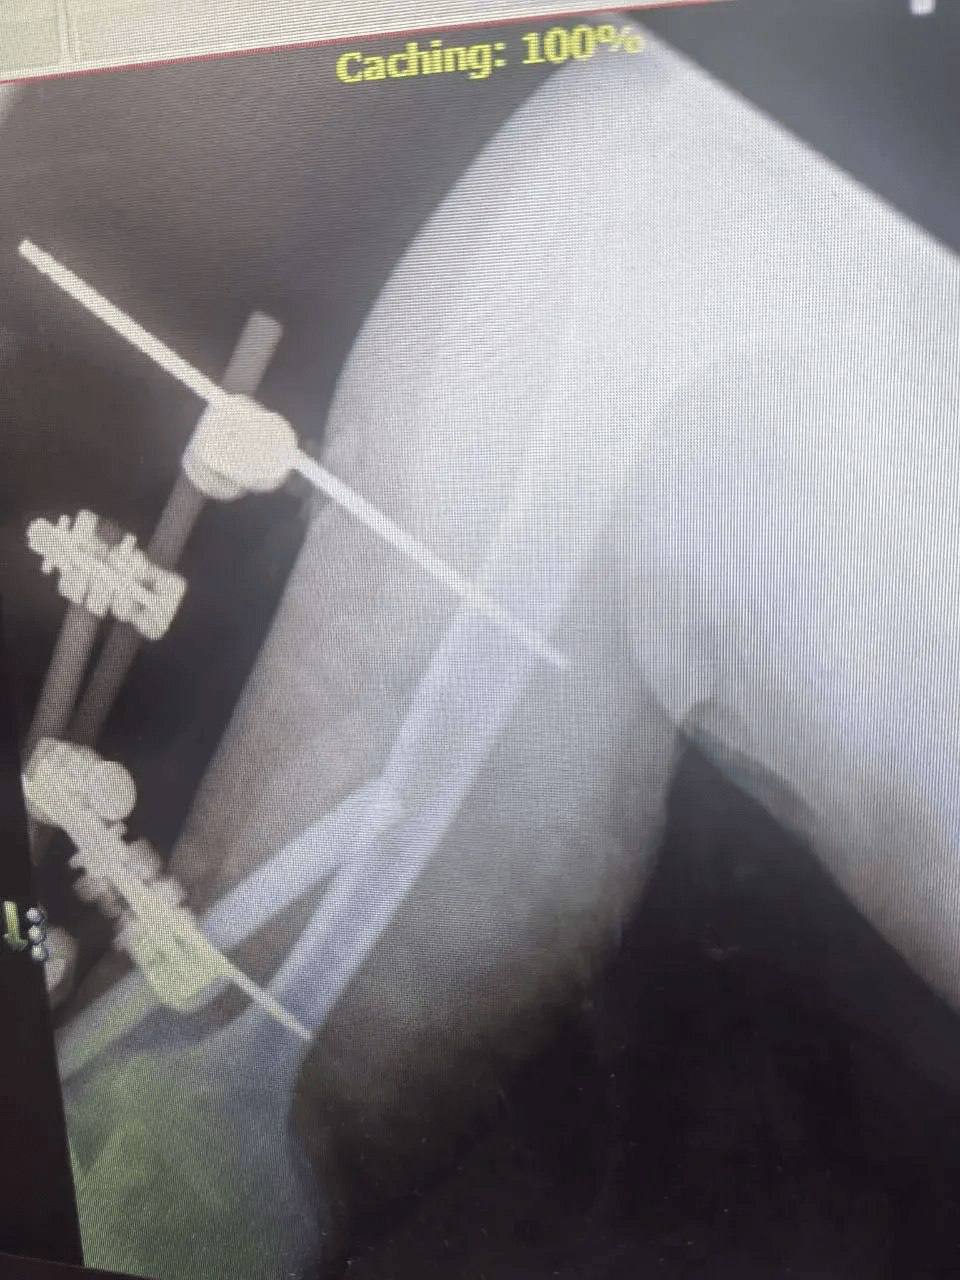

В больницу скорой помощи поступил 52-летний мужчина с тяжёлой политравмой после падения. У него были множественные переломы и повреждения, требующие комплексного лечения.

К работе подключилась команда специалистов: челюстно-лицевые хирурги, травматологи, нейрохирурги и неврологи провели операции и терапию. Несмотря на осложнение в виде токсического гепатита, врачам удалось стабилизировать состояние пациента.